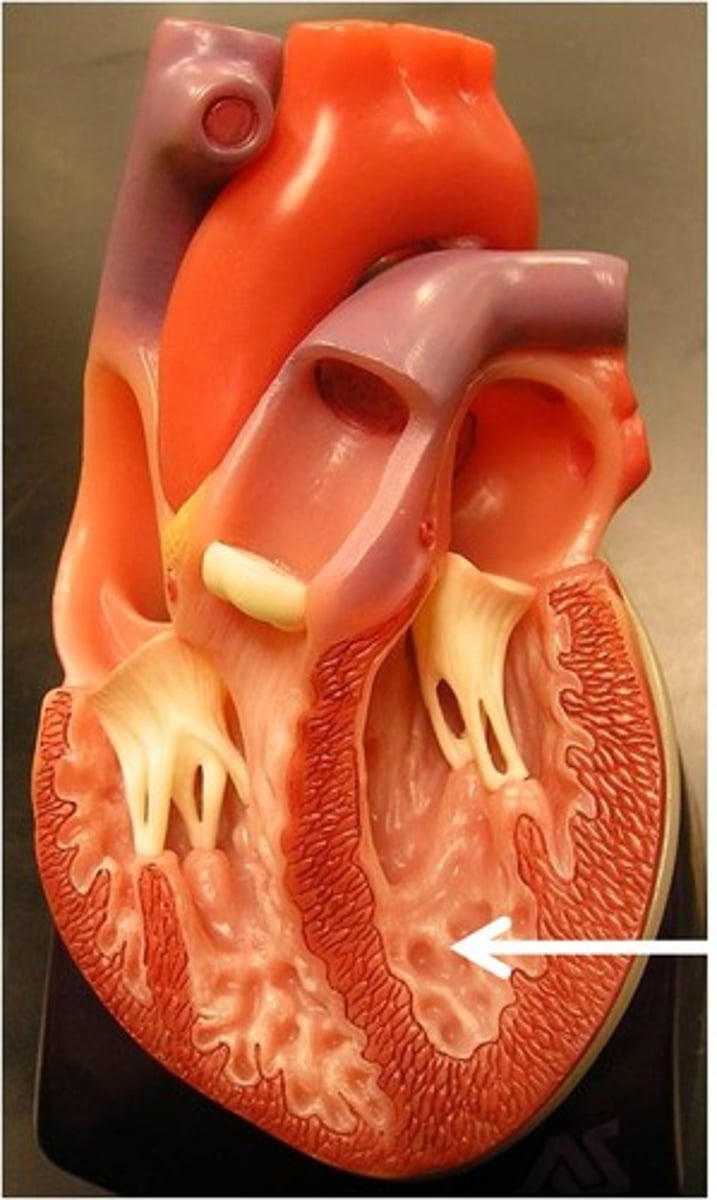

Trabeculae carneae

Ridged wall of the ventricles (contracts)

Papillary muscles

Have chordae tendineae that are attached to the valve flaps so they don't prolapse

From: Left atrium through the bicuspid valve

To: Aorta through semilunar valve to systemic system

From: Right atrium through tricuspid valve

To: Pulmonary trunk (artery) through semilunar valve to lungs then pulmonary veins

Atrioventricular valves (tricuspid and bicuspid)

Prevents back flow into atria

Semilunar valves (aortic and pulmonary)

Prevents back flow into ventricles

Both have three flaps

Don't have papillary muscles

False, the changes in pressure open and close the AV valves

True or False: The contraction and relaxation of the papillary muscles open and close the AV valves

True

True or False: The ventricles and papillary muscles contract concurrently